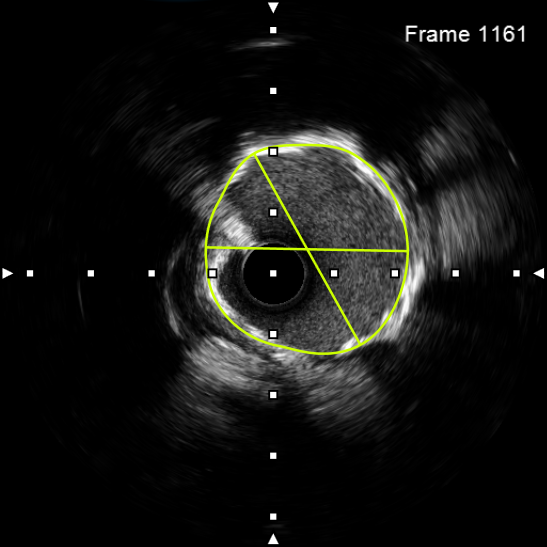

该患者入院后,完善相关检查并再次建议行CABG治疗,但家属仍拒绝,遂考虑再次行PCI手术干预。冠脉造影提示患者冠脉右冠状动脉中段70-95%再狭窄,左主干末端80%狭窄,前降支原支架中远段 80-95%再狭窄,回旋支完全闭塞,急需手术尽快解决冠脉血流灌注问题,否则随时有生命风险,但患者多处支架内/节段内再狭窄,造影提示钙化明显,外院已尝试无法扩张,经手术团队充分讨论后,计划在IABP支持下,先进行右冠状动脉干预,利用IVUS精准评估原支架再狭窄部位情况,采用旋磨或Shockwave冲击波球囊处理无法扩张的病变部位,右冠处理后择期进行左冠状动脉干预。在制定了详尽的手术计划后,手术团队首先对患者的右冠状动脉行IVUS检查,结果提示该患者右冠中段支架局部膨胀不良,局部支架面积6.67mm²,管腔内多处可见钙化小结及270°以上钙化,IVUS钙化积分达3分。由于膨胀不良处原支架后方可见钙化斑块,常规旋磨效果不佳,对于此类钙化病变,IVL处理是最佳方案。手术团队对近端采取棘突球囊及高压球囊进行扩张,采用Guidezilla辅助下输送3.0mmx12mm Shockwave冲击波球囊于右冠钙化处进行冲击波钙化斑块碎裂术,通过IVUS证实支架内的新生钙化病变得到松解,原膨胀不良部位支架面积达到7.76mm²,后经过高压球囊充分预处理,顺利完成右冠支架植入,术后复查右冠原膨胀不良部位支架面积9.17mm²。

图3 IVUS示右冠中段支架膨胀不良,支架内多处可见新生钙化病变